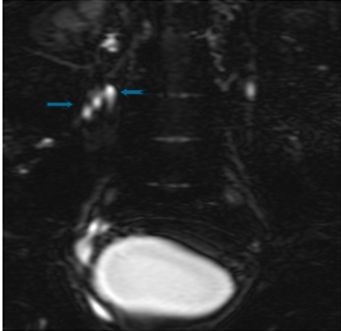

Figure 2 (a,b,c): MR Urography image

shows the two laterally placed right lower ureters, fuse at the level of L4

vertebral body (

) and terminate into

the vesico-ureteric junction; whereas the single upper moiety ureter terminates

ectopically into the neck of the bladder (

)